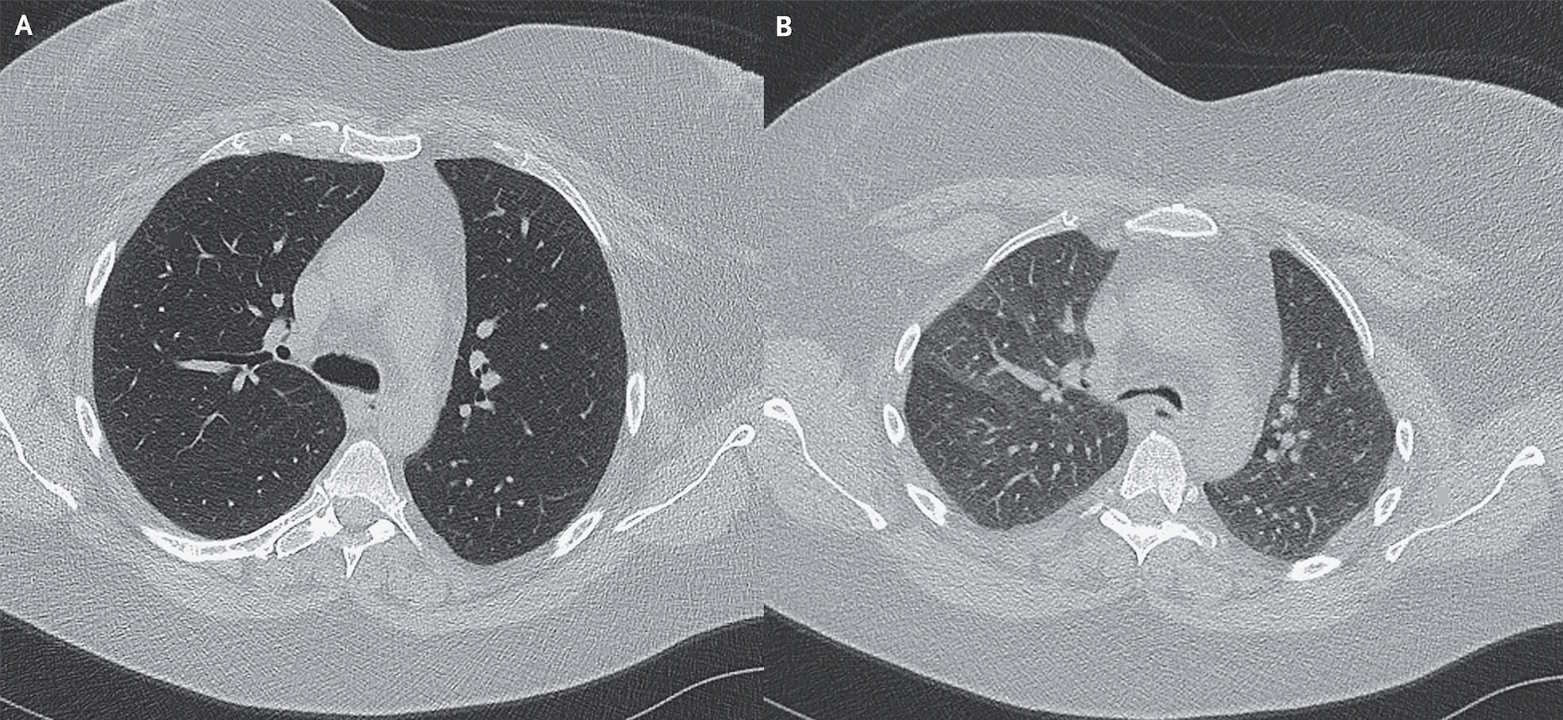

У пацієнтки діагностували колапс дихальних шляхів: коли вона видихала (В), її трахея та бронхи звужувалися на 70 відсотків порівняно зі вдихом (А).

Щоб встановити діагноз, пацієнтці провели динамічну комп’ютерну томографію грудної клітини, протягом якої фіксували стан і положення органів на різних етапах вдиху та видиху. У жінки виявили вигин задньої стінки трахеї та верхньої частини бронхів, через що на видиху вони закривалися на 70 відсотків, порівняно зі вдихом. Пацієнтку залишили в лікарні на тиждень, де провели очищення легень від слизу та давали вночі дихати повітрям під тиском. Після цього симптоми в жінки зникли, а її саму спрямували на програму реабілітації, яка включала роботизовану операцію.